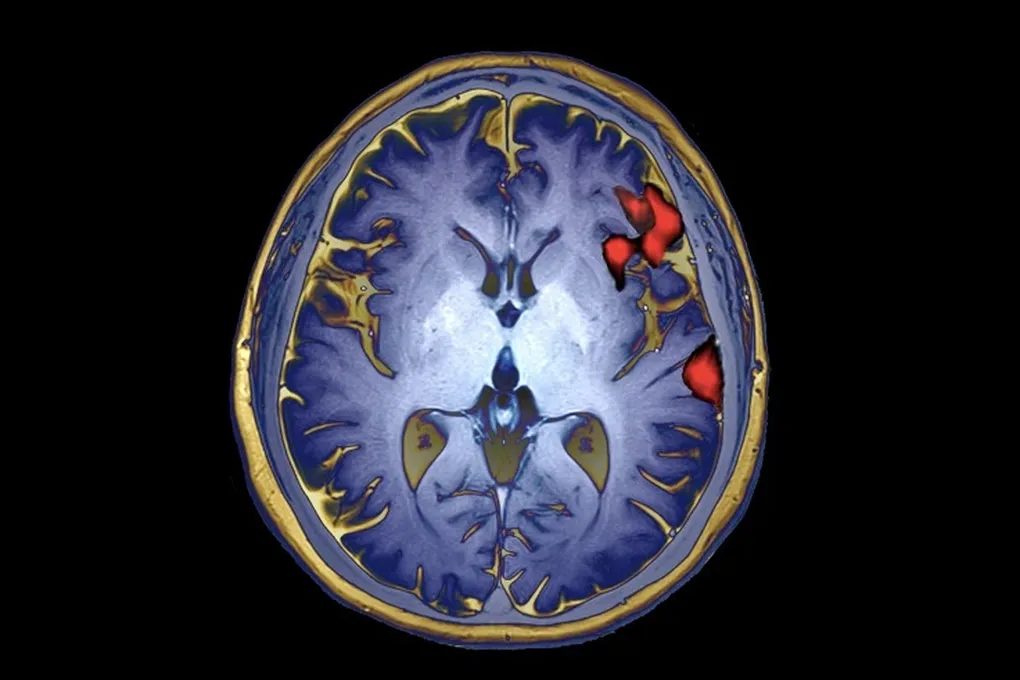

Самое удивительное открылось, когда ученые начали анализировать данные с электродов. Раньше, используя неинвазивные методы вроде фМРТ, нейробиологи приходили к выводу, что разные языки активируют разные участки мозга. Но прямой доступ к нейронам всё перевернул с ног на голову.

Оказалось, что когда Панчо думает на испанском или английском, основные всплески активности происходят в одном и том же речевом центре. Более того, паттерны его мозговой активности удивительно похожи на те, что наблюдаются у людей, выросших с двумя языками с детства.